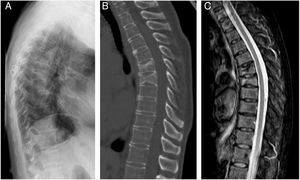

ResultsThe characteristics of the patients are shown in Table 1. Their average age at the start of treatment was 66 ± 7.7 years. Four patients had a previous history of fractures due to fragility, and only one had risk factors for secondary OP (aromatase inhibitors, case 7). Nine patients (90%) had received other treatments prior to commencing with DMab (7 oral bisphosphonates, 5 strontium ranelate, 2 raloxifene, 1 tibolone and 1 calcitonine). The patients received from 3 to 9 doses of DMab, following the dosage recommended in its technical data sheet, with an average of 6 ± 1.7. The reason for withdrawal of the drug was dental work (cases 1 and 6), low risk of fracture (case 5) and termination of the time set by the prescribing doctor. In all cases except two bone density had been measured before starting with DMab. The average T-score before treatment was -2.6 ± 0.6 in the femoral neck (FN) and -3.0 ± 1.3 in the lumbar spine (LS). Likewise, in all of the cases except two (cases 7 and 9) densitometry was performed at least 6 months after the withdrawal of the treatment, with an average T-score of -3.2 ± 0.7 in the FN and -3.2 ± 1.6 in the LS. The bone turnover markers at least 10 months after discontinuation were found to be high, with a collagen telopeptide average (CTX) of 1.32 ± 0.32 ng/ml, and collagen propeptide (P1NP) of 181.6 ± 104.1 ng/ml. The time between the last dose of the drug and the appearance of the first fracture varied from 8 to 18 months, with an average of 10.9 ± 3.3 months. The patients suffered from 2 to 9 fractures, and a total of 49 fractures were recorded. Fig. 1 shows the diagnostic imaging tests corresponding to case 10. In all cases the fractures occurred spontaneously, without associated trauma. The vertebras affected the most often were L3, L5, D6, D7, D9 and D11. Two patients (cases 1 and 2) received vertebroplasty, and new vertebral fractures occurred in both patients. One patient (case 9) commenced taking alendronate six months after discontinuing DMab, following the recommendations of the European Calcified Tissue Society (ECTS), and in spite of this suffered vertebral fractures (Fig. 2). Respecting the pharmacological treatment received after the fractures, the options used the most often were teriparatide (30%), oral bisphosphonates (20%) and DMab (20%).

In our series one patient received alendronate 6 months after the discontinuation of DMab, following ECTS recommendations, and she suffered 9 new fractures after this measure. The ETCS recommends starting treatment with another anti-osteoporosis agent when DMab treatment is discontinued: administering a single dose of zoledronic acid or oral bisphosphonate during at least one year.10 Before the publication of these recommendations, patients who discontinued DMab often received no alternative treatment for OP, above all if they had attained their target level of osteopenia without any new fractures. In our series the doctor in charge of the patients considered in 7 cases (7/10, 70%) that they had taken DMab for a suitable length of treatment. With the subsequent acquired knowledge of the efficacy and safety of treatment with DMab and with the FREEDOM extension study data,11,12 it is possible that a current review of the risk of fracture in patients who discontinued treatment would have led us to prolong the treatment with DMab. Nor can we rule out the possibility that the risk of fracture remained high in some of our who treatment had been discontinued. It is relevant that two patients discontinued treatment to undergo dental work, as this centres the problem in the need for suitable anti-rebound discontinuation guides that are shared with stomatologists. The latest SER recommendations for osteoporosis in patients treated with anti-rebound agents who are about to undergo a dental procedure do not recommend discontinuing treatment with bisphosphonates or DMab. If there are risk factors for maxillary osteonecrosis and the surgical procedure will be extensive, the possibility of discontinuation is only considered in the case of the bisphosphonates.13